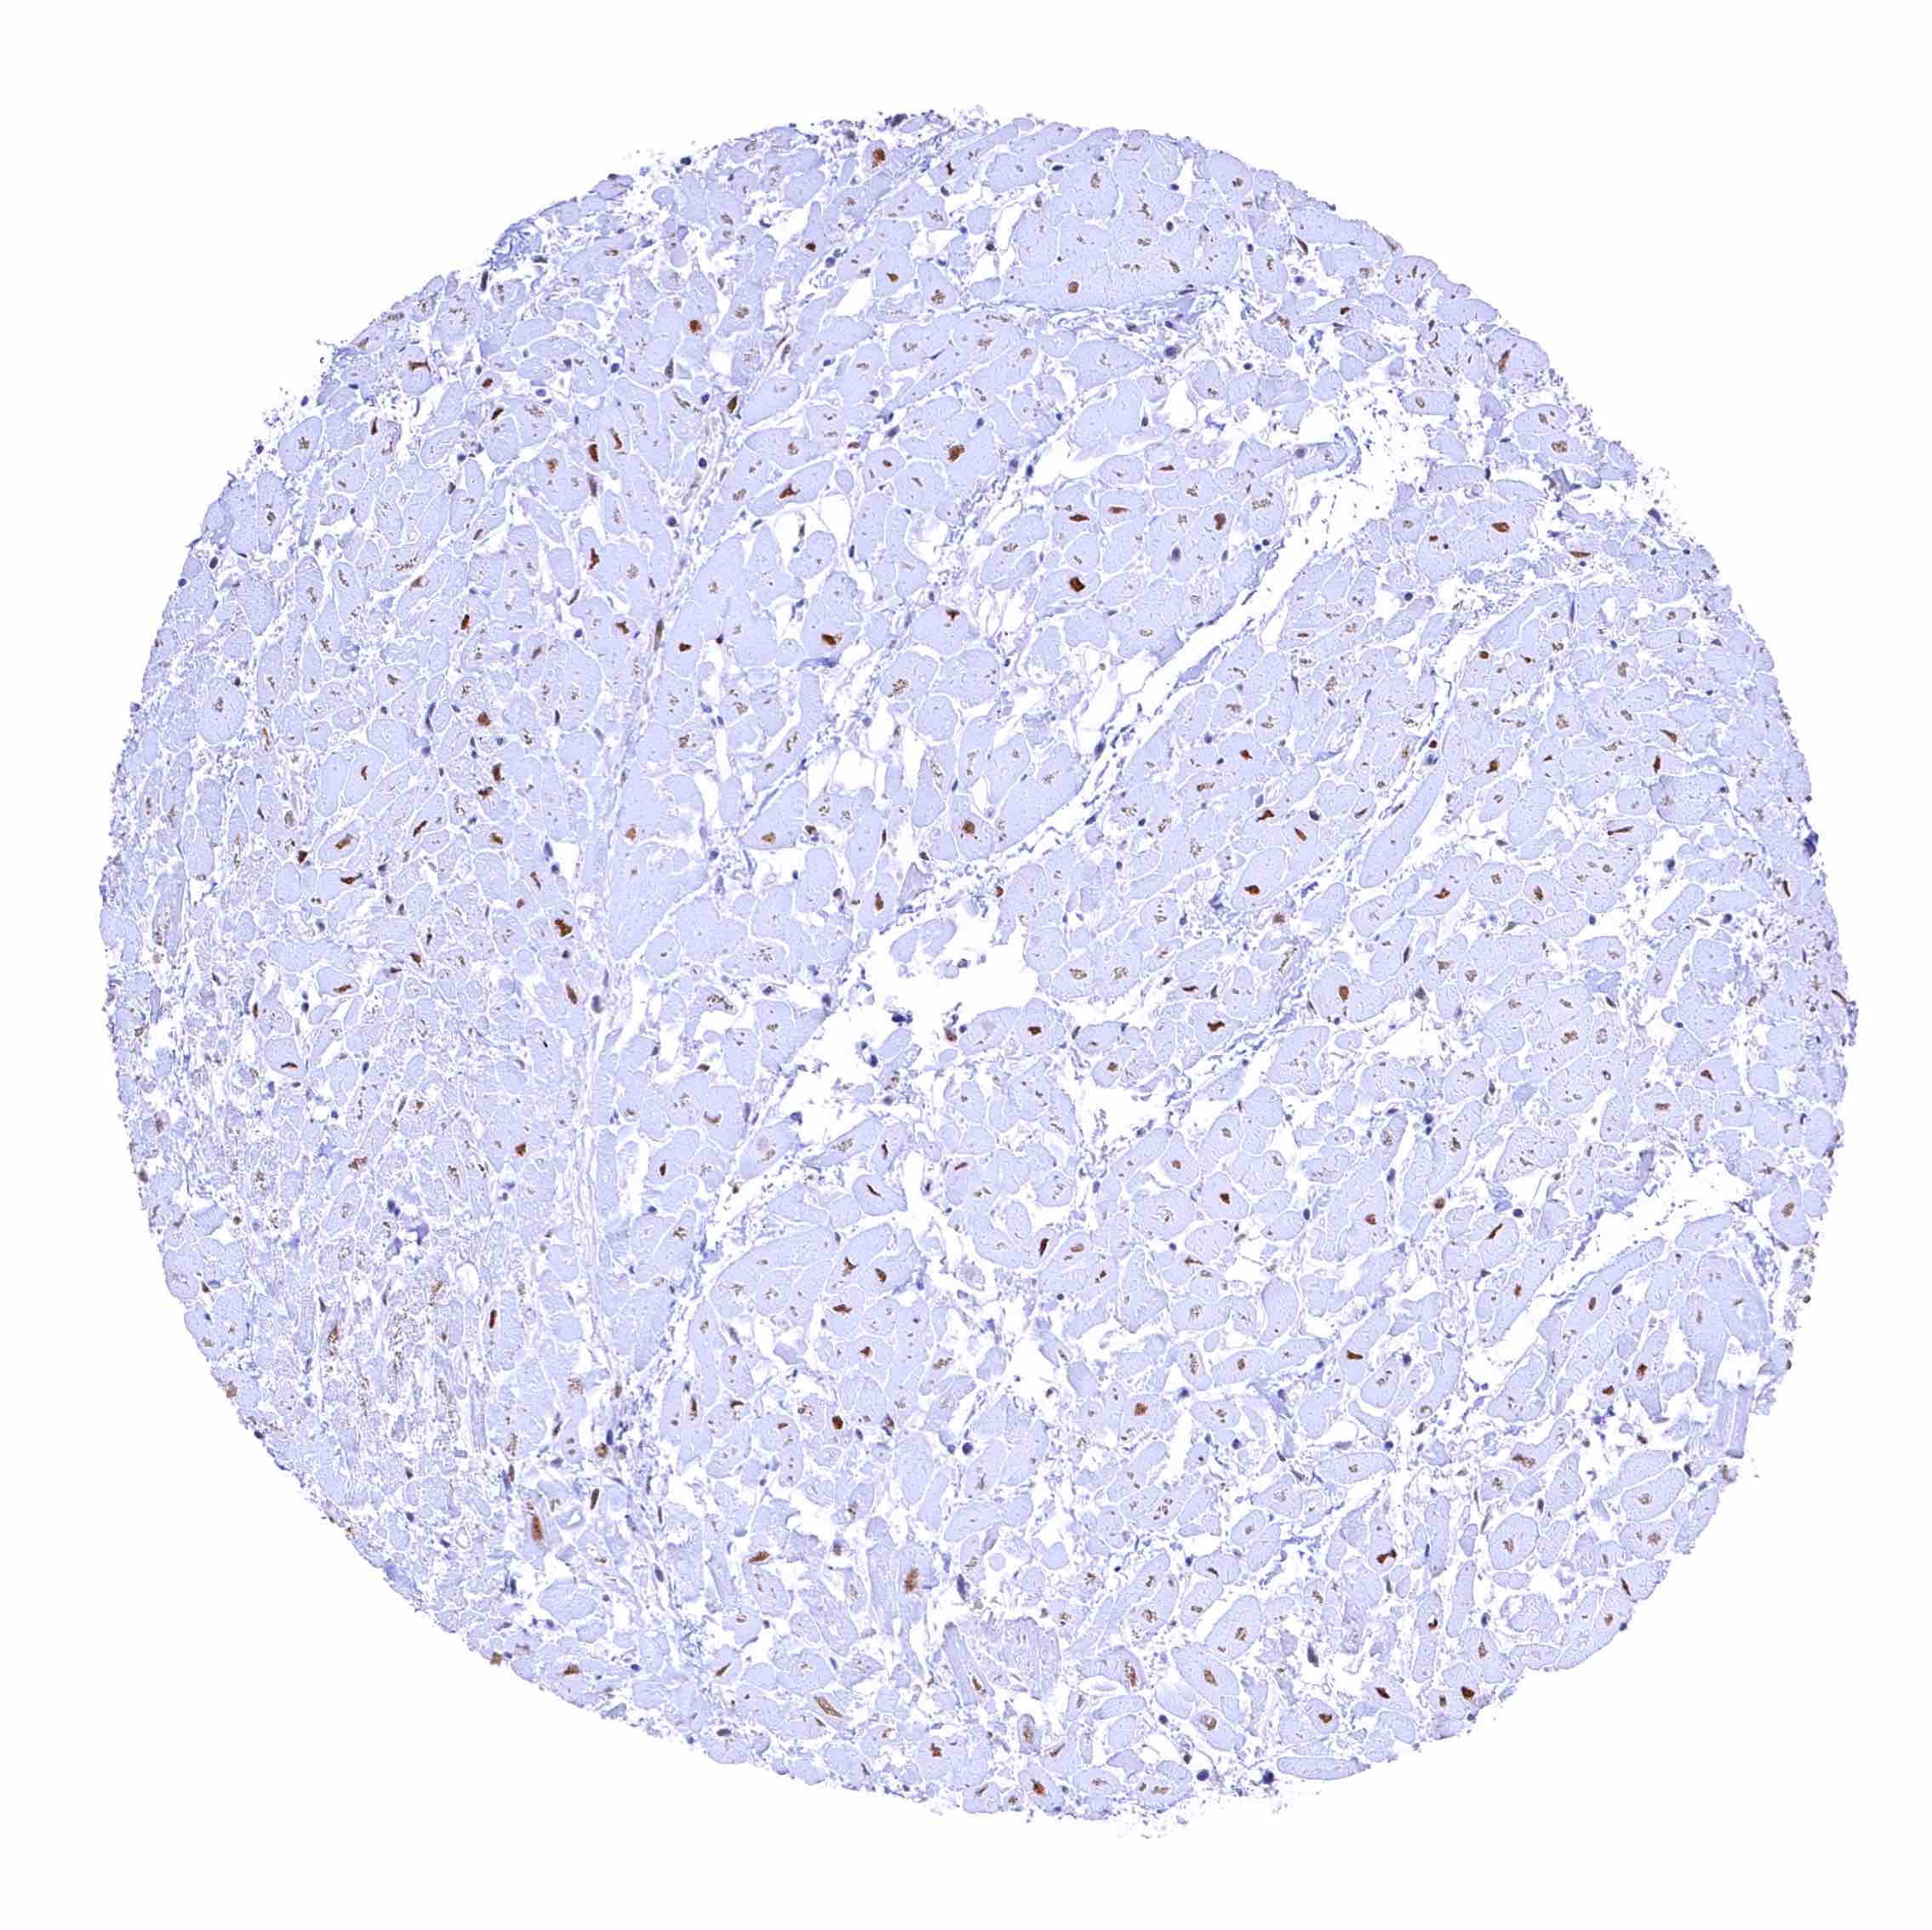

Heart muscle